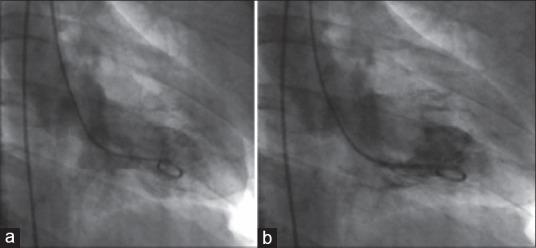

We describe a case of Takotsubo cardiomyopathy in a case of pituitary macroadenoma in acute adrenal crisis. A 48-year-old man presented with acute onset altered sensorium, vomiting, and gasping. On admission, he was unresponsive and hemodynamically unstable. He was intubated and ventilated and resuscitated with fluids and inotropes. The biochemical evaluation revealed hyponatremia, hyperkalemia, and hypocortisolism. Hyponatremia was corrected with 3% hypertonic saline. Contrast enhanced computed tomography (CT) scan of the brain revealed a sellar-suprasellar mass with hypothalamic extension with no evidence of pituitary apoplexy. A diagnosis of invasive pituitary adenoma with the Addisonian crisis was made and steroid replacement was initiated. Despite volume resuscitation, he had persistent refractory hypotension, recurrent ventricular tachycardia, and metabolic acidosis. Electrocardiogram (ECG) showed ST elevation and T-wave inversion in lateral leads; cardiac-enzymes were increased suggestive of acute coronary syndrome. Transthoracic echocardiography showed severe regional wall motion abnormalities (RWMAs) involving left anterior descending territory and low ejection fraction (EF). Coronary angiogram revealed normal coronaries, apical ballooning, and severe left ventricular dysfunction, consistent with a diagnosis of Takotsubo's cardiomyopathy. Patient was managed with angiotensin-converting enzyme inhibitors and B-blockers. He improved over few days and recovered completely. At discharge, ECG changes and RWMA resolved and EF normalized to 56%. In patients with Addisonian Crisis with persistent hypotension refractory to optimal resuscitation, possibility of Takotsubo's cardiomyopathy should be considered. Early recognition of association of Takotsubos cardiomyopathy in neurological conditions, prompt resuscitation, and supportive care are essential to ensure favorable outcomes in this potentially lethal condition.

我们描述了一例垂体大腺瘤合并急性肾上腺危象患者发生的Takotsubo心肌病。一名48岁男性,急性起病,出现意识改变、呕吐和喘息。入院时,他无反应且血流动力学不稳定。予以气管插管、机械通气,并给予液体和血管活性药物进行复苏。生化检查显示低钠血症、高钾血症和皮质醇减少。低钠血症用3%高渗盐水纠正。脑部增强计算机断层扫描(CT)显示鞍区-鞍上肿块并累及下丘脑,无垂体卒中迹象。诊断为侵袭性垂体腺瘤合并艾迪生病危象,并开始进行类固醇替代治疗。尽管进行了容量复苏,但他仍持续存在难治性低血压、反复发作的室性心动过速和代谢性酸中毒。心电图(ECG)显示侧壁导联ST段抬高和T波倒置;心肌酶升高提示急性冠状动脉综合征。经胸超声心动图显示严重的节段性室壁运动异常(RWMA)累及左前降支区域,射血分数(EF)降低。冠状动脉造影显示冠状动脉正常、心尖部气球样变和严重的左心室功能障碍,符合Takotsubo心肌病的诊断。患者接受血管紧张素转换酶抑制剂和β受体阻滞剂治疗。几天后病情好转并完全康复。出院时,心电图改变和RWMA消失,EF恢复正常至56%。对于艾迪生病危象且经最佳复苏后仍持续低血压的患者,应考虑Takotsubo心肌病的可能性。早期认识到Takotsubo心肌病在神经系统疾病中的关联、及时复苏和支持治疗对于确保这种潜在致命疾病的良好预后至关重要。